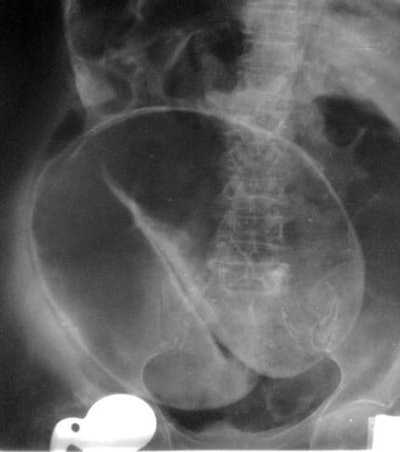

Coffee bean: This characteristic sign of sigmoid volvulus consists of a greatly distended, air-filled loop of sigmoid colon extending from the pelvis on abdominal radiography. The medial walls of the dilated bowel form a distinct oblique line that resembles the cleft of a coffee bean. It arises from the pelvis and may be large, with its apex often extending above the level of T10 to the left or right of the midline.

Coffee bean sign with perforation.